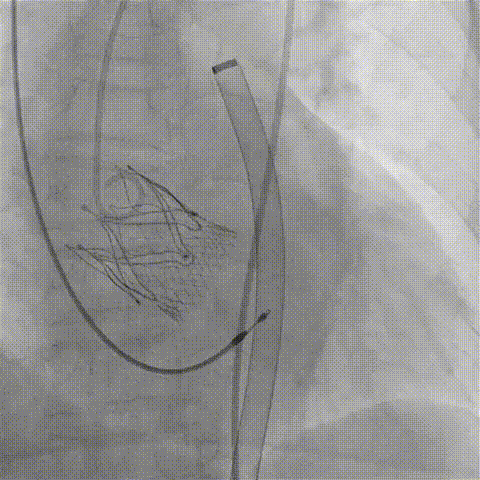

2026年伊始,TaurusTrio经导管主动脉瓣系统在复旦大学附属中山医院,浙江大学医学院附属第二医院,中国医学科学院阜外医院,首都医科大学附属北京安贞医院,四川大学华西医院等多家临床中心成功开展上市后全国首批植入。这不仅是TaurusTrio正式走向广泛临床应用的重要里程碑,更标志着中国单纯主动脉瓣反流介入治疗正式迈入了“心键合璧”的全新纪元。